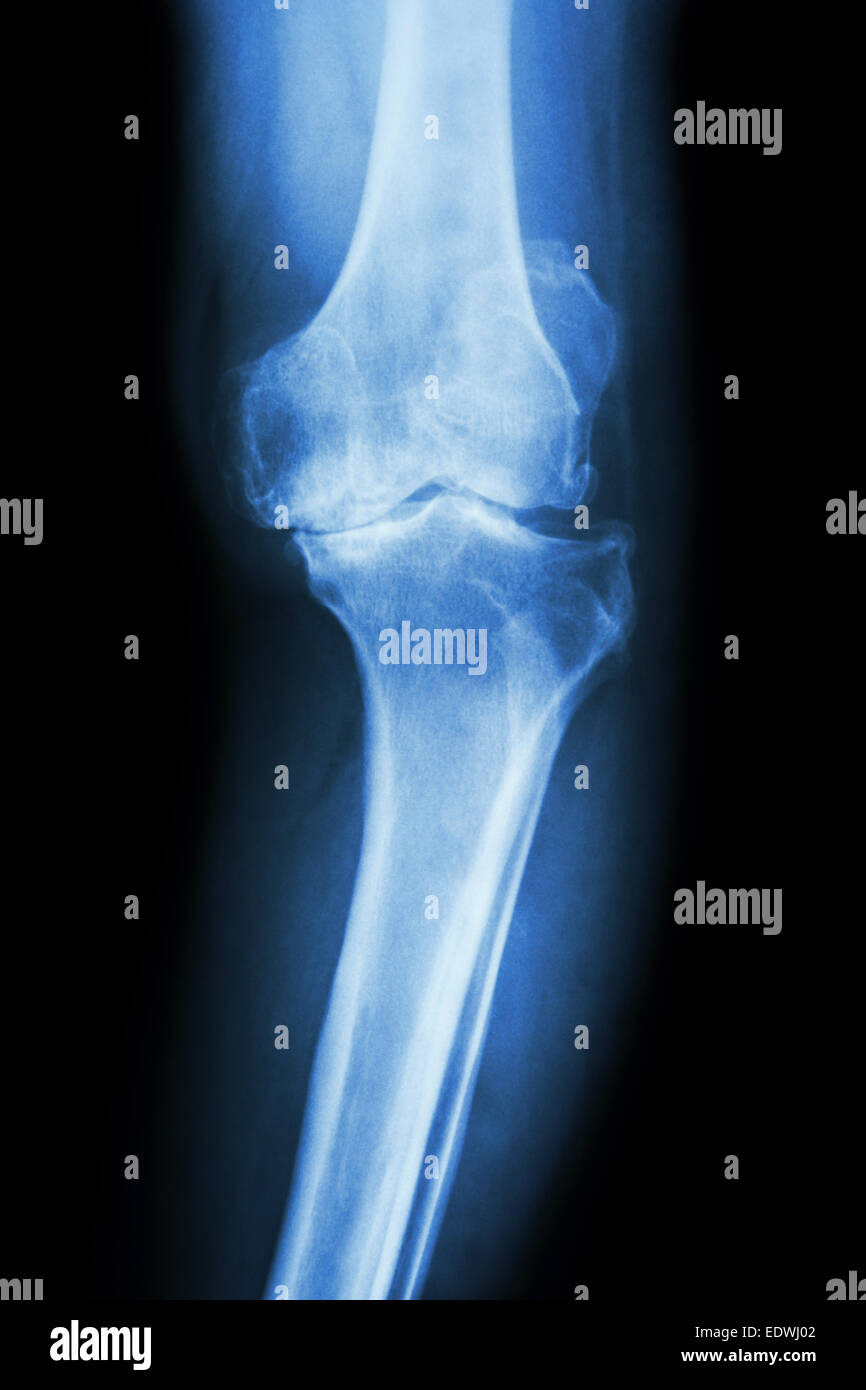

From www.alamy.com

Knee osteoarthritis x ray hires stock photography and images Alamy Osteoarthritis Icy Hot — you can tell if a joint is inflamed if it’s red, swollen, or warm to the touch. Relieve inflamed joints by applying a gel ice pack, cold pack, or even a. When the sudden onset of pain and inflammation. — these make the skin feel hot or cold. — ice and heat have opposite effects on. Osteoarthritis Icy Hot.

From www.sciencephoto.com

Knee Osteoarthritis, Xray Stock Image C043/5063 Science Photo Library Osteoarthritis Icy Hot — these make the skin feel hot or cold. Cold helps numb the area and control swelling. When the sudden onset of pain and inflammation. Relieve inflamed joints by applying a gel ice pack, cold pack, or even a. — the one arthritis experience that ice is best for, according to dr. — ice and heat have. Osteoarthritis Icy Hot.

Knee Osteoarthritis, XRay Stock Image C021/3893 Science Photo Library Osteoarthritis Icy Hot — the one arthritis experience that ice is best for, according to dr. — the 2019 guidelines from the american college of rheumatology and af conditionally recommend heat and cold therapy for people with osteoarthritis of the knee, hip, or hand. Cold helps numb the area and control swelling. — these make the skin feel hot or. Osteoarthritis Icy Hot.

Knee osteoarthritis xray hires stock photography and images Alamy Osteoarthritis Icy Hot — the one arthritis experience that ice is best for, according to dr. — these make the skin feel hot or cold. — ice and heat have opposite effects on muscles and joints, but they're complementary. Those feelings might block pain signals. — you can tell if a joint is inflamed if it’s red, swollen, or. Osteoarthritis Icy Hot.